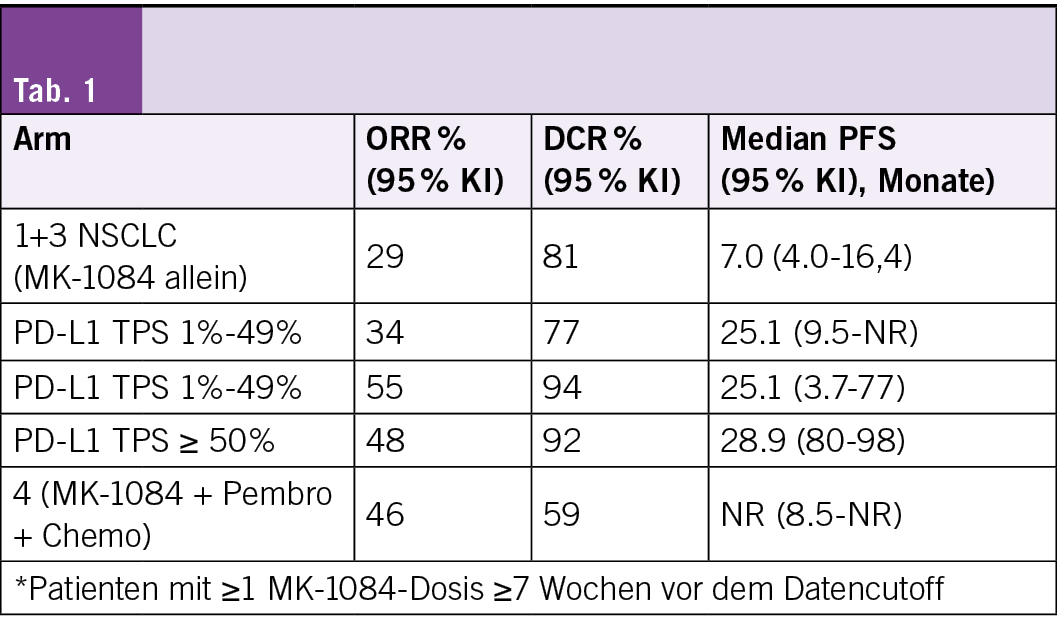

MK-1084 + Pembrolizumab zeigte in der KANDLELIT-001-Studie eine klinisch bedeutsame Wirksamkeit

Adrian Sacher, et al. 4MO Updated results for MK-1084 + pembrolizumab in KRAS G12C-mutated (mut) metastatic non-small cell lung cancer (mNSCLC) enrolled in KANDLELIT-001

Vorbemerkung

Die Phase-I-Studie KANDLELIT-001 (NCT05067283) bestätigt laut Forschern, dass der orale, selektive KRAS-G12C-GDP-Kovalenzinhibitor der nächsten Generation MK-1084 ein gutes Sicherheitsprofil aufweist und vielversprechende Antitumoraktivität zeigt. Er wurde entweder allein oder in Kombinationstherapie bei Patienten mit soliden Tumoren, die eine KRAS-G12C-Mutation besitzen, eingesetzt.

Die Autoren berichten über aktualisierte Daten für Patienten mit KRAS-G12C-mutiertem mNSCLC.

Studiendesign

• Patienten in den Armen 1 und 3 wiesen einen beliebigen KRAS-G12C-mutierten soliden Tumor mit mindestens einer vorangegangenen systemischen Therapie auf und erhielten eine MK-1084-Monotherapie mit 25–800 mg/Tag.

• Patienten in Arm 2 hatten unbehandeltes mNSCLC mit einem PD-L1-TPS von ≥ 1 % und erhielten MK-1084 25–400 mg/Tag + Pembrolizumab 200 mg alle 3 Wochen.

• Patienten in Arm 4 hatten unbehandeltes nicht-squamöses mNSCLC und erhielten MK-1084 50–200 mg/Tag + Pembrolizumab 200 mg, Carboplatin und Pemetrexed alle 3 Wochen.

• Dosislimitierende Toxizitäten (DLTs) und Sicherheit waren primäre Endpunkte; ORR, DCR und PFS gemäss RECIST v1.1 nach Beurteilung durch den Prüfer waren sekundäre Endpunkte.

Behandlungsresultate

• Zum Datencutoff am 23. Juli 2025 befanden sich 146 Patienten in den Armen 1 und 3, darunter 32 (22 %) mit mNSCLC, 87 Patienten in Arm 2 und 46 Patienten in Arm 4.

• Die mediane Nachbeobachtungszeit betrug 27,9 Monate, 14,1 Monate, 14,6 Monate bzw. 12,1 Monate. Die ORR in Arm 2 (MK-1084 + Pembro) betrug 92 % (TPS = 50 %), bei einem entsprechenden medianen PFS von 29 Monaten (Vergleiche Tabelle im Originalabstract).

• 15 (10 %) Patienten in den Armen 1 und 3, 26 (30 %) Patienten in Arm 2 und 28 (61 %) Patienten in Arm 4 wiesen arzneimittelbedingte unerwünschte Ereignisse (UE) des Grades 3–4 auf, darunter jeweils 3 %, 8 % und 11 % mit erhöhten ALT-Werten des Grades 3–4 sowie 3 %, 9 % und 9 % mit erhöhten AST-Werten des Grades 3–4.

• 1 Patient verstarb an einer arzneimittelbedingten Myelosuppression und einer verminderten Thrombozytenzahl (Arm 2) und 1 an einer arzneimittelbedingten immunvermittelten Myositis (Arm 4).

Fazit

MK-1084 zusammen mit Pembrolizumab erzielte in der KANDLELIT-001-Studie laut Studienautoren eine klinisch bedeutende Wirksamkeit – insbesondere zeigte sich bei Patienten mit PD-L1-TPS = 50 % eine Ansprechrate von über 90 %. Die Nebenwirkungen waren kontrollierbar; die Rate schwerwiegender ALT/AST-Erhöhungen blieb unter 10 %. Das insgesamt positive Verhältnis zwischen Nutzen und Risiko unterstützt die weitere Untersuchung in der laufenden Phase-III-Studie KANDLELIT-004. Dort wird MK-1084 + Pembrolizumab als Erstlinientherapie gegen Placebo + Pembrolizumab bei KRAS-G12C-mutiertem mNSCLC mit PD-L1-TPS = 50 % verglichen.